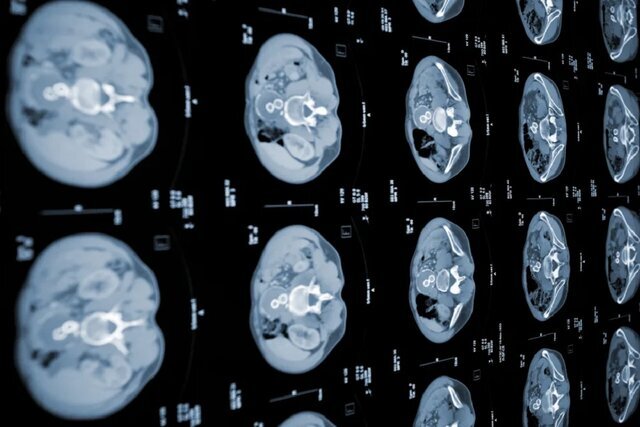

متخصصان موسسه فناوری ماساچوست(MIT) مدل هوش مصنوعی جدیدی را توسعه داده‌اند که می‌تواند سرطان لوزالمعده(پانکراس) را پیش از آن که دیر شود، تشخیص دهد.

تشخیص زودهنگام سرطان لوزالمعده با مدل جدید هوش مصنوعی

به گزارش آگاه: پژوهشگران موسسه فناوری ماساچوست(MIT) که بر مهندسی رایانه و توسعه هوش مصنوعی تمرکز دارد، دو الگوریتم یادگیری ماشینی ساخته‌اند که می‌تواند سرطان لوزالمعده را زودتر از استانداردهای تشخیصی فعلی تشخیص دهد.

این دو مدل هوش مصنوعی جدید با هم برای ایجاد یک شبکه عصبی موسوم به PRISM و تشخیص آدنوکارسینوم مجرای لوزالمعده(PDAC) که شایع‌ترین شکل سرطان لوزالمعده است، طراحی شده و شکل گرفته‌اند.